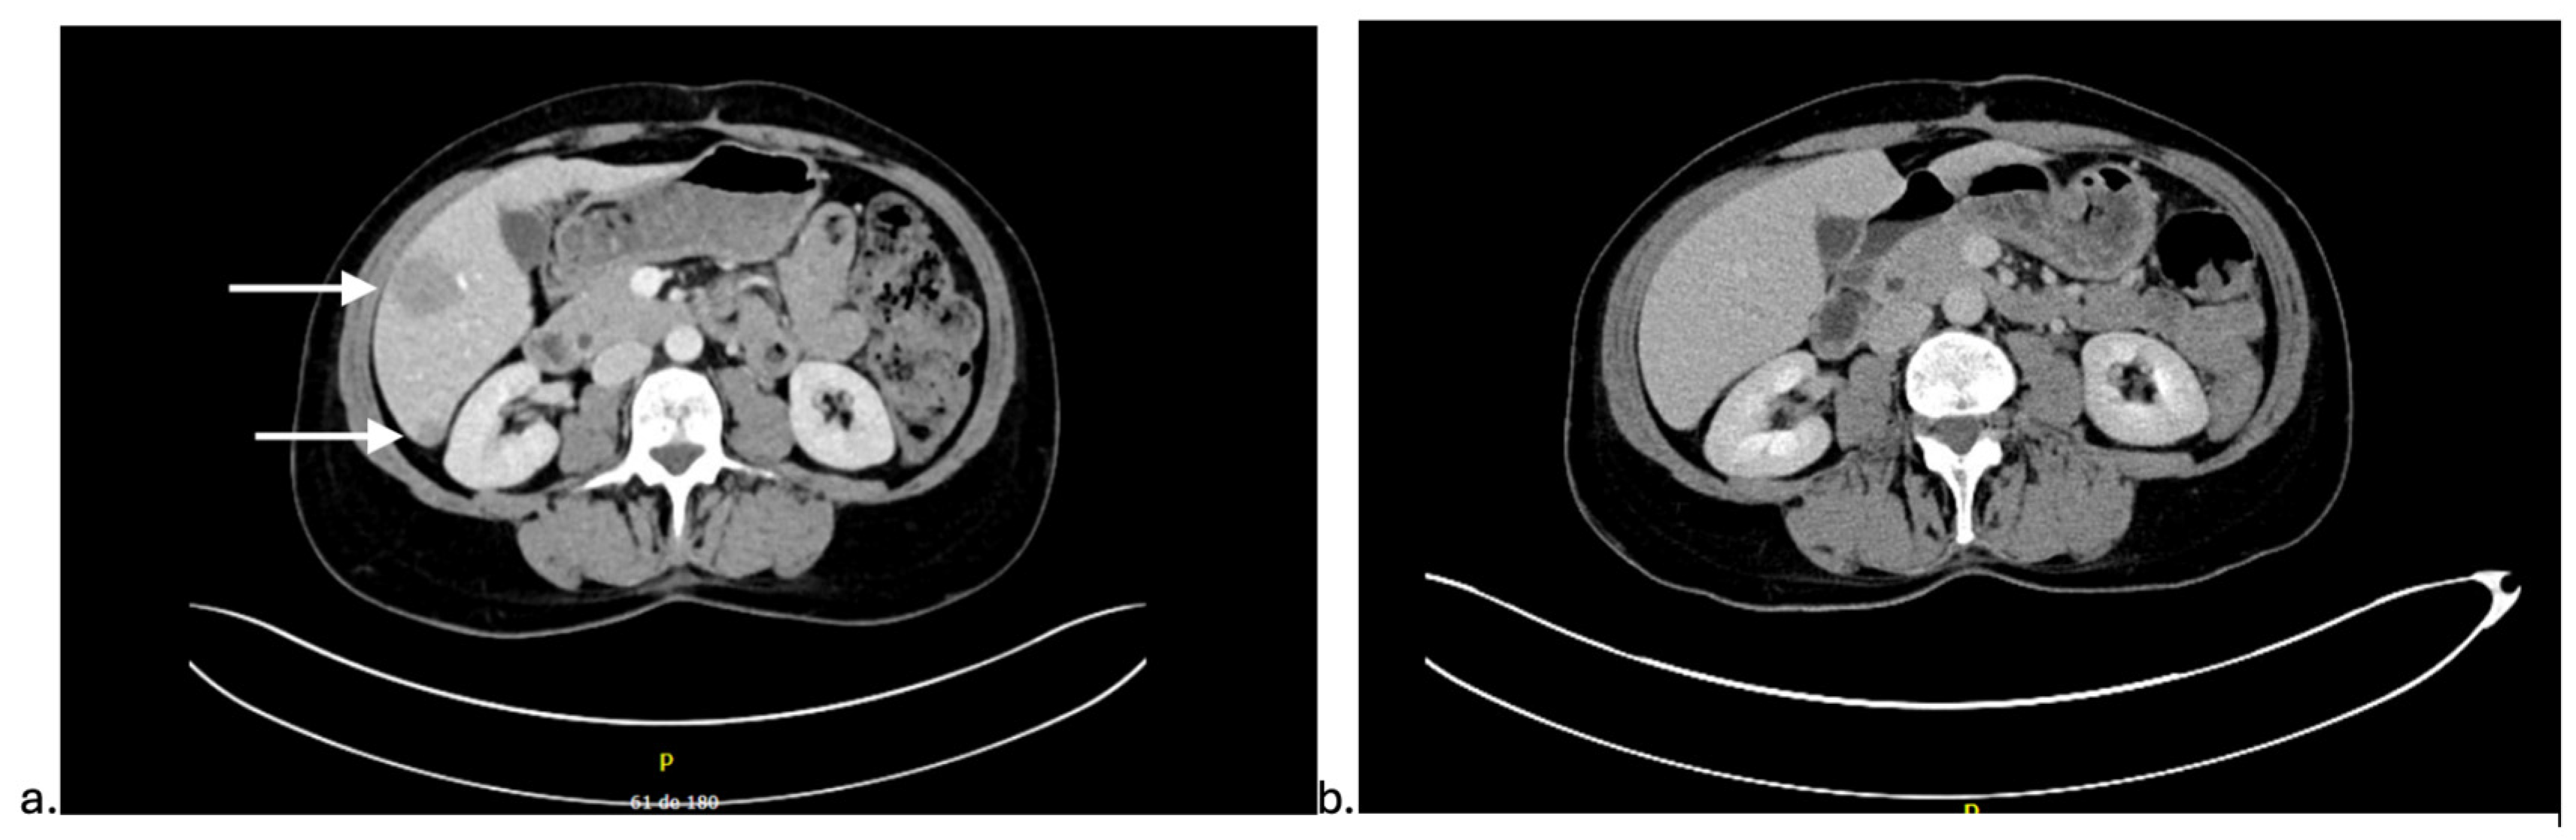

2. Detailed Case Description